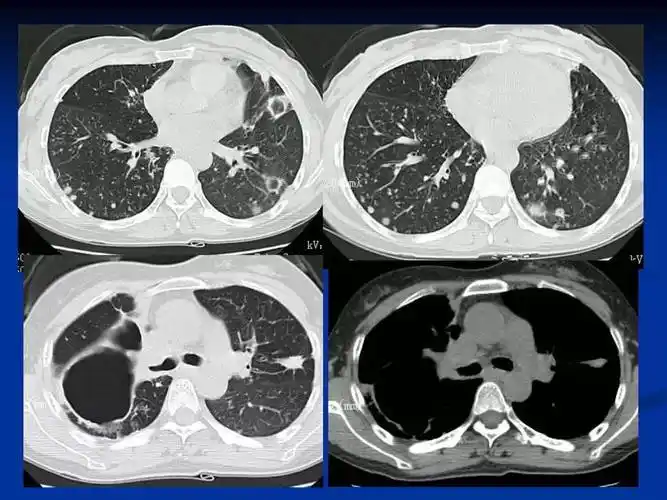

肺结核的影像诊断与鉴别